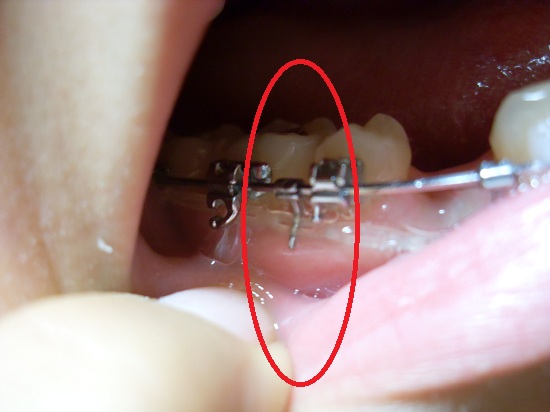

저기 고무줄 때문에 잇몸이 살짝 내려간거 보이시나요?

치과를 가서 잇몸을 누르던 고무줄을 빼주시구 새로운 게 하나 더 생겼어요.

저기 동그라미 친 부분 보이시나여! 새로운 막대기가 하나 생겼어요

고무줄이 잇몸을 누르지 않게 도와준답니다 ♥ 흐억 너무 조아요